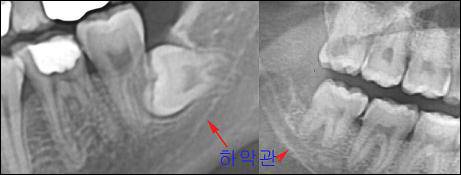

사진에서 붉은 화살표로 표시한 것은 '하악관'이라 불려지는 구조물로 그 안에 신경(하치조 신경)과 동맥이 들어 있다. 사진에서처럼 사랑니의 뿌리 끝과 매우 가까운 경우가 많고 따라서 신경 손상의 위험은 늘 존재한다.

다행스러운 것은 하치조 신경의 경우 방사선 사진으로 대략적인 위치를 알 수 있고 그림에서처럼 직접 신경 다발을 자를 가능성이 높지 않다는 점이다. 손상 원인은 대부분 사랑니의 머리를 자를 때 발생하는 열과 압력 또는 이가 뽑힐 때의 외력이 뼈를 타고 안에 있는 신경에게 전달돼 스트레스를 준 것에 있기 때문에, 대개 6개월~1년 사이에 원상 복구된다.

사진에서 알 수 있 듯이 혀신경은 뼈속이 아닌 피부 사이를 지나가며 근육에 의해서조차 보호 받지 못하고 사랑니의 바로 옆을 지나갈 가능성도 20%나 된다. 뼈로 둘러쌓여 있지 않기 때문에 MRI가 아닌 일반 방사선 사진으로는 신경이 지나가는 곳을 짐작할 수 있는 어떤 단서도 얻을 수 없는 것 역시 문제다.